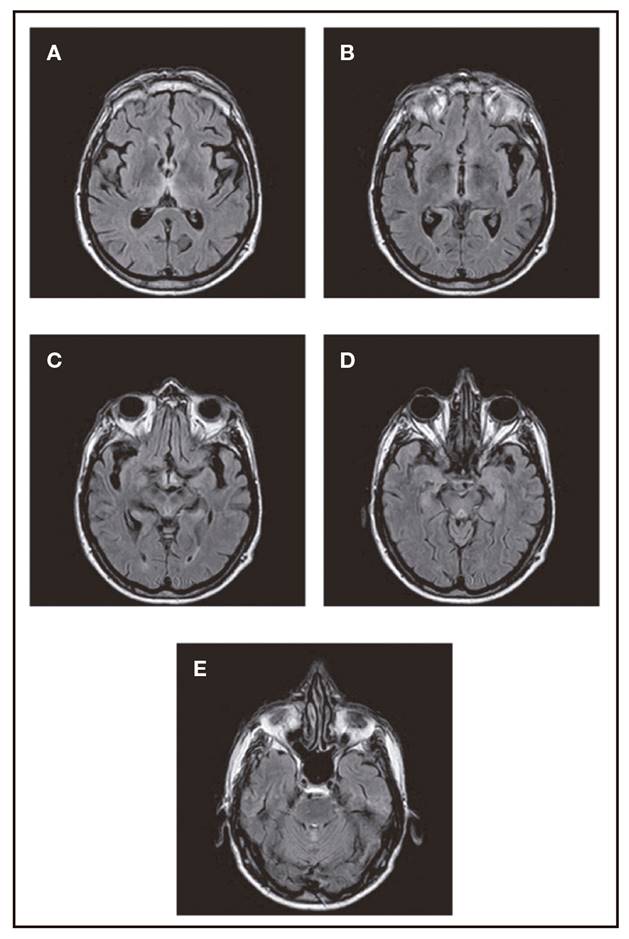

En algo más de la mitad de los pacientes la resonancia magnética en T2 y FLAIR muestra hiperseñales talámicas, periacueductales y en el techo del IV ventrículo.

Ante la gravedad del cuadro, y tras descartar otras causas de pericarditis, optamos por considerar que se trataba de un proceso sistémico disinmune o carencial, y se inició tratamiento simultáneamente con inmunoglobulina humana inespecífica y tiamina. A las 48 h de tratamiento, la mejoría era marcada. La RM craneal, que mostraba las alteraciones características del SWK, a las dos semanas se había normalizado. Alta al mes del ingreso, con mínima tetraparesia, hipoestesia en guante y calcetín y ataxia moderada (precisaba de andador). A los cinco meses había podido cambiar el andador por un bastón. No quedaron secuelas cognitivas.